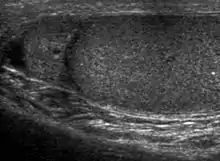

Normal epididymal head. The epididymal head, usually iso- or slightly hyperechoic than the testis is seen located cephalad to the testis.

The normal adult testis is an ovoid structure measuring 3 cm in anterior-posterior dimension, 2–4 cm in width, and 3–5 cm in length. The weight of each testis normally ranges from 12.5 to 19 g. Both the sizes and weights of the testes normally decrease with age. At ultrasound, the normal testis has a homogeneous, medium-level, granular echotexture. The testicle is surrounded by a dense white fibrous capsule, the tunica albuginea, which is often not visualized in the absence of intrascrotal fluid. However, the tunica is often seen as an echogenic structure where it invaginates into the testis to form the mediastinum testis. In the testis, the seminiferous tubules converge to form the rete testes, which is located in the mediastinum testis. The rete testis connects to the epididymal head via the efferent ductules. The epididymis is located posterolateral to the testis and measures 6–7 cm in length. At sonography, the epididymis is normally iso- or slightly hyperechoic to the normal testis and its echo texture may be coarser. The head is the largest and most easily identified portion of the epididymis. It is located superior-lateral to the upper pole of the testicle and is often seen on paramedian views of the testis. The normal epididymal body and tail are smaller and more variable in position.